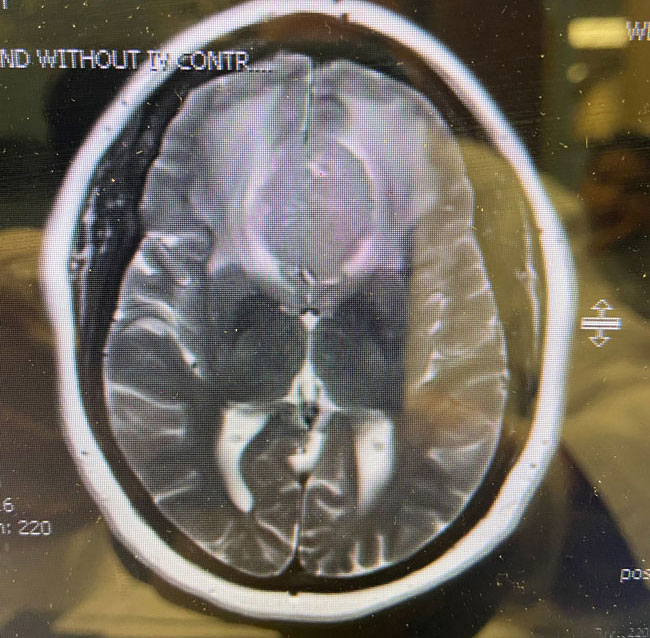

This is a 64 year-old woman with no significant past medical history who noted rapid deterioration of vision in her left eye 3 weeks earlier. She said it felt like there was a cloud over her eye. Ophthalmology evaluation confirmed poor vision in the left eye and ordered a brain MRI. The MRI demonstrated a large planum sphenoidale meningioma with significant compression on the optic nerves and optic chiasm and significant surrounding edema (Figures 1 a, b, and c). She was then referred to Dr. Michael Brisman for neurosurgical evaluation.